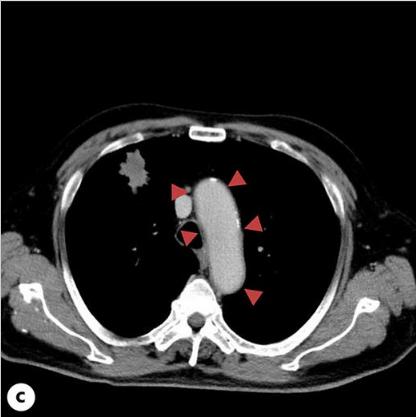

患者接受了卡铂/依托泊苷/杜伐单抗(Dur)和PEG-G-CSF的全剂量组合治疗,重点是剂量强度。在施用PEG-G-CSF后10天施用第四剂冠状病毒疫苗。在PEG-G-CSF给药后的第12天,出现38℃的发热和右耳疼痛,这种情况没有改善,并在第17天就诊。血液检查显示炎症反应明显升高,白细胞计数为15600/μL,C-反应蛋白为33.9 mg/dL,白细胞介素6 (IL-6)水平为114 pg/mL。然而,对整个躯干和头部的物理检查和简单的CT未能检测出发热源或炎症反应升高的原因(图一a)。虽然患者没有出现FN,但不能排除细菌感染的可能性,立即住院并使用了氨苄西林/舒巴坦。第二天对整个躯干进行的CE-CT显示主动脉弓降胸主动脉周围的脂肪组织密度增加,提示主动脉炎(图一b)。患者抗中性粒细胞胞浆抗体和其他自身抗体检测呈阴性。有乙型/丙型肝炎病毒(HBV/丙型肝炎病毒)感染史,入院后有退热趋势,并接受过ICIs治疗。因此,在没有全身皮质类固醇治疗的情况下,仅用解热镇痛药并进行了仔细的随访。第20天,患者体温改善至36°C,右耳疼痛和炎症反应逐渐改善,第33天的对比CT显示主动脉周围炎症表现改善(图一C,2)。那时血清IL-6水平降至8.7 pg/mL。由于免疫相关不良事件的可能性仍然存在,卡铂/依托泊苷的剂量减少到80%,Dur在第二个疗程的化疗中被停用。患者的病情进展顺利,除了白细胞计数略有下降。剂量减少的卡铂/依托泊苷以4周的间隔继续治疗,患者的进展良好,没有主动脉炎发作的迹象。

图1、患者的CT图像。A、PEG-G-CSF给药后第17天拍摄的胸部平面CT图像。此图像没有显示主动脉周围阴影增加。B、在PEG-G-CSF给药的第18天获得的胸部对比增强(CE)-CT扫描。此图显示主动脉周围阴影增加,提示主动脉炎。C、在PEG-G-CSF给药的第33天进行胸部CE-CT扫描。如图中的红色三角形所示,主动脉周围的阴影比图B中所示的要小